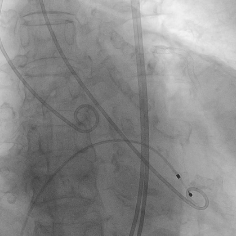

双侧股动脉穿刺建立工作路径,送入猪尾导管行主动脉根部造影,交换Safari导丝后将瓣膜输送系统送入升主动脉。输送系统柔顺过弓后顺利将31mm J-VALVE TF瓣膜推至主动脉根部。释放定位件,其可自动定位、轻松准确入窦。定位件入窦后,再次进行造影,在多角度投照下确认瓣膜位置稍高,遂将瓣膜稍向下推,调整至合适位置后将瓣膜释放。瓣膜释放后即刻复查主动脉根部造影,显示瓣膜支架位置稳定、形态展开良好,同轴性佳,未见主动脉瓣反流及瓣周漏,手术顺利结束。瓣膜植入过程仅用时5-10分钟。

主动脉根部造影

瓣膜输送系统过弓,至主动脉根部

定位件释放

定位件入窦后造影

瓣膜释放

瓣膜释放后造影